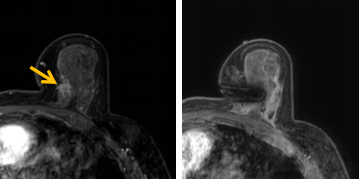

患者李女士磁共振檢查發(fā)現(xiàn)右乳內(nèi)側(cè)高度可疑病變,病變小摸不到,超聲和X線攝影(鉬靶)都看不到,怎么辦?要想明確病變性質(zhì),必須進行磁共振引導(dǎo)下精準足量的活檢,但是這種技術(shù)操作難度大、軟硬件要求高。

經(jīng)過仔細查體并分析所有影像資料,陳寶瑩發(fā)現(xiàn),病變靠近胸大肌,容易造成術(shù)中損傷。患者乳房較小,病變在內(nèi)側(cè),導(dǎo)致乳房不易固定,進針難度大,與患者充分溝通后,陳寶瑩帶領(lǐng)團隊,制定了細致的操作方案,術(shù)中,醫(yī)護團隊反復(fù)調(diào)整體位和固定架的角度及方向,利用隔離技術(shù)保護好周圍組織。受乳房形態(tài)和病變位置的限制,醫(yī)生只能蹲著、跪著進行操作,經(jīng)過30多分鐘終于順利完成,精準獲取了足量的組織,而且一針到位,創(chuàng)傷小、出血少,患者沒有任何不適,做完即回家休息。幾天后,病理證實是一種特殊類型的早期乳腺癌,為后續(xù)進一步治療方案的制訂提供了準確依據(jù)。

陳寶瑩教授介紹,乳腺磁共振微創(chuàng)診療技術(shù)是針對磁共振發(fā)現(xiàn)的可疑病變,進行磁共振引導(dǎo)的導(dǎo)絲定位、旋切活檢、靶釘植入及消融治療的微創(chuàng)診療技術(shù)。磁共振特有的多模態(tài)和功能成像,不但能顯示出更多其他檢查發(fā)現(xiàn)不了的可疑病變,而且能顯示出病變準確的范圍和活性區(qū)域,因此MR引導(dǎo)的乳腺病變真空輔助旋切技術(shù)相較于其他常規(guī)活檢技術(shù),具有更精準、活性成分取材充足的特點,明顯降低了病理的假陰性率,提高了準確性。